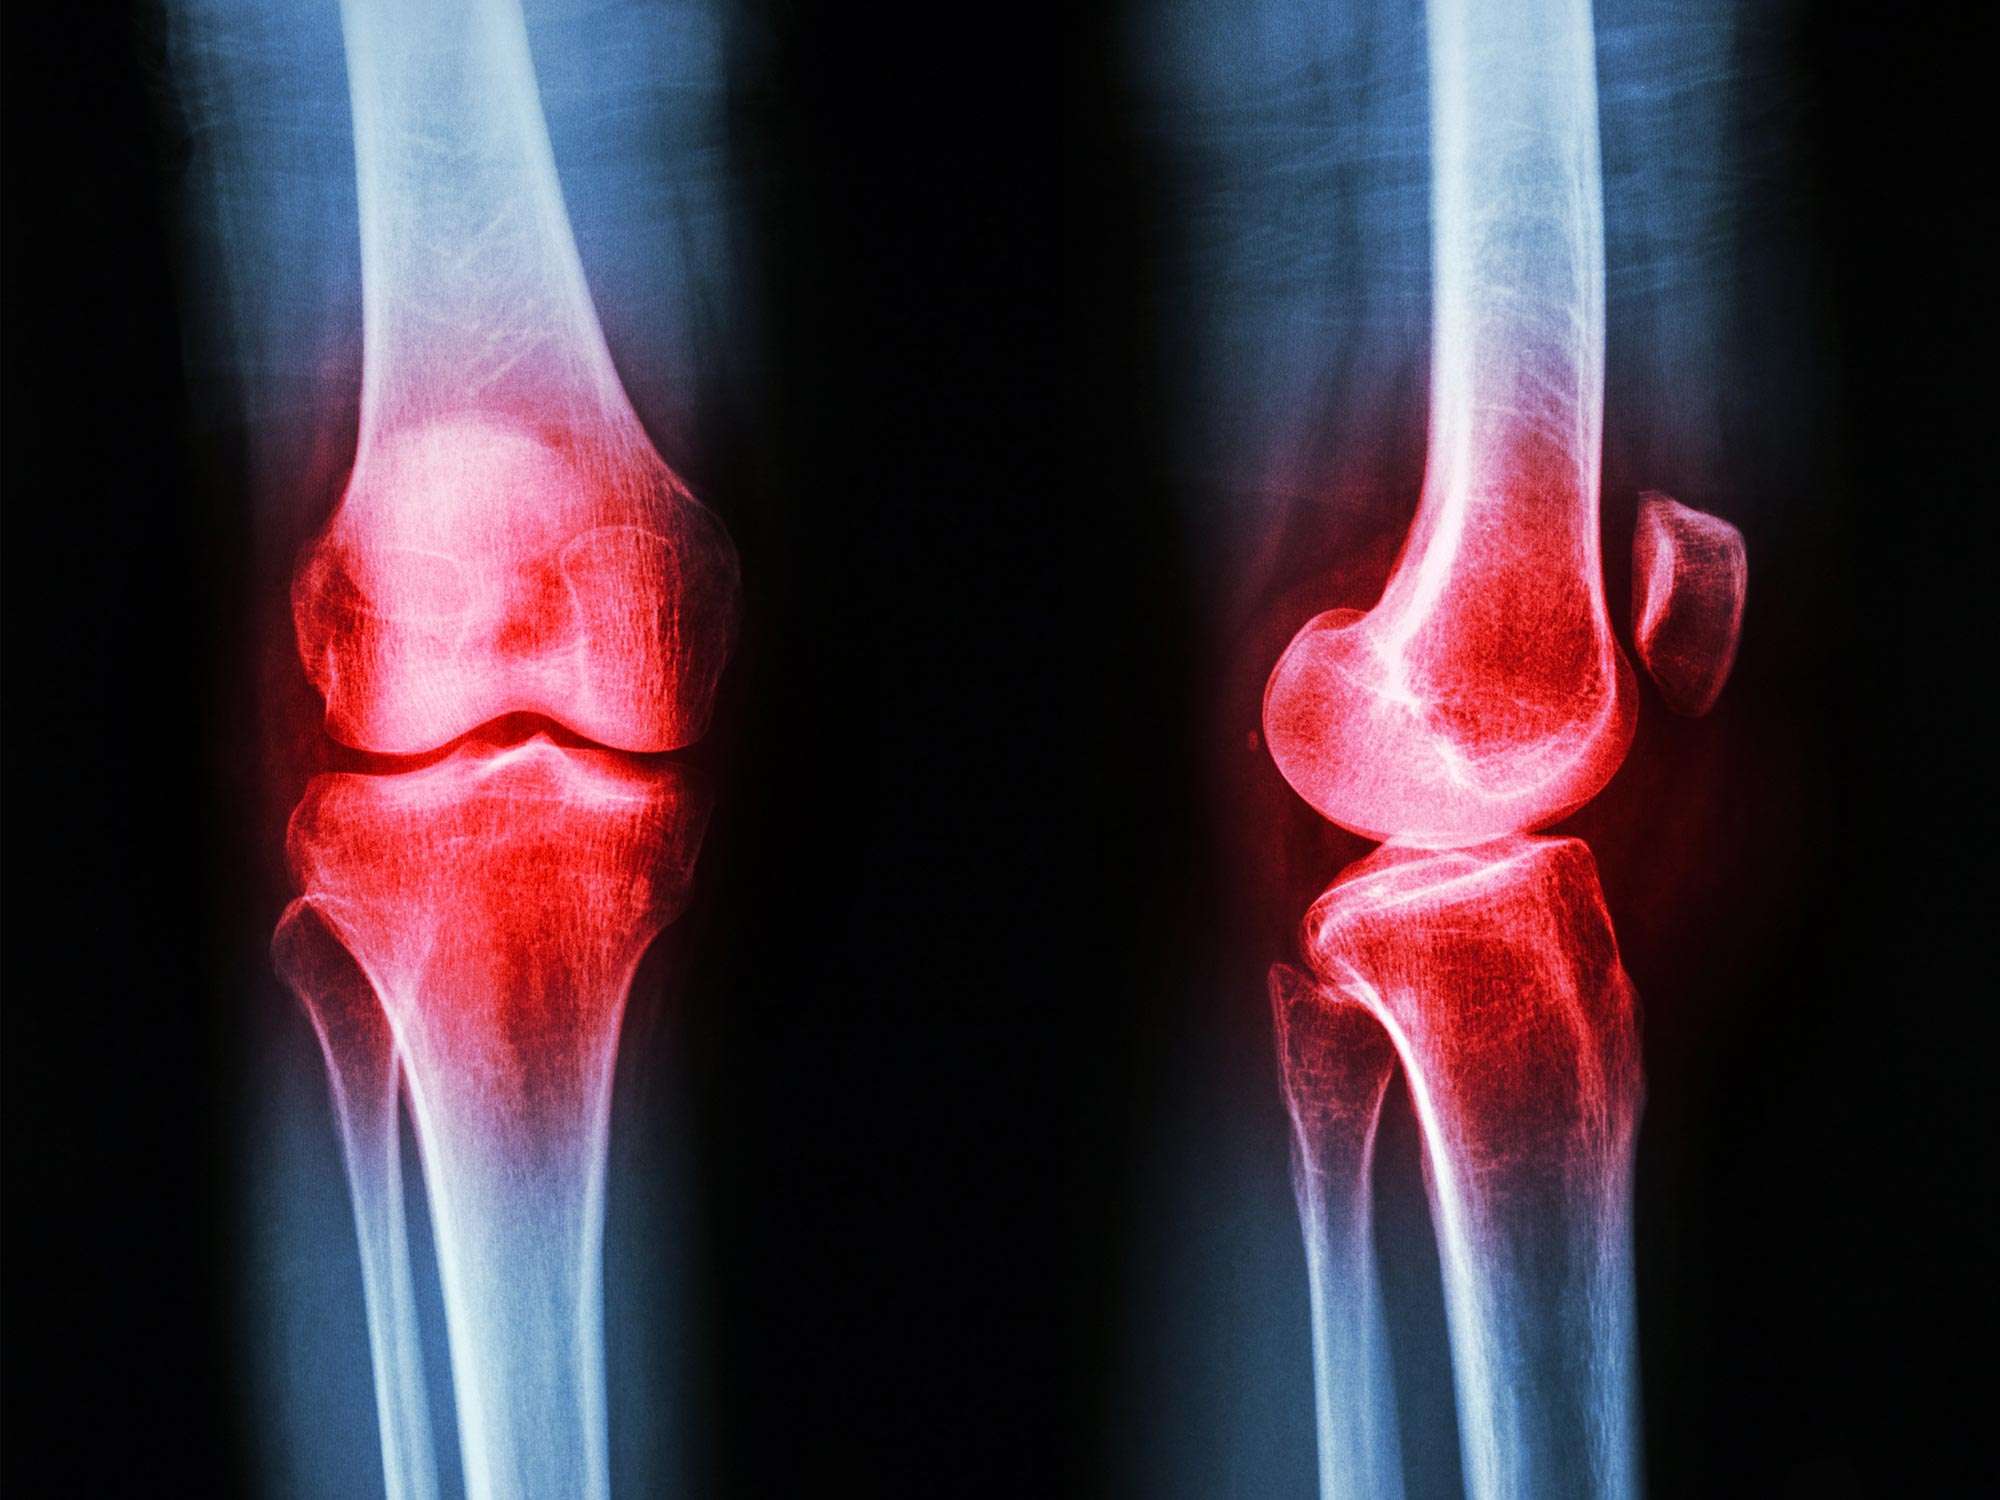

Knee joint of a patient showing (A) severe cartilage defects and (B) intact knee joint. Credit: RSNA and Upasana Upadhyay Bharadwaj, M.D.

Osteoarthritis is a degenerative joint disease that causes the cartilage in the joints to crack down, main to soreness, stiffness, and issue shifting. It is a popular problem that normally impacts the arms, knees, hips, and spine. Threat things for acquiring osteoarthritis consist of getting old, weight problems, and a history of joint accidents.

Osteoarthritis is a prevalent situation that impacts 32.5 million grownups in the United States and is characterised by the degeneration and breakdown of cartilage in the joints. Knee osteoarthritis, which affects around 800,000 people each 12 months, is a chronic and progressive affliction that can bring about soreness and issue transferring. Somewhere around 10{2c3a8711102f73ee058d83c6a8025dc7f37722aad075054eaafcf582b93871a0} of persons with knee osteoarthritis find noninvasive solutions and switch to corticosteroid or hyaluronic